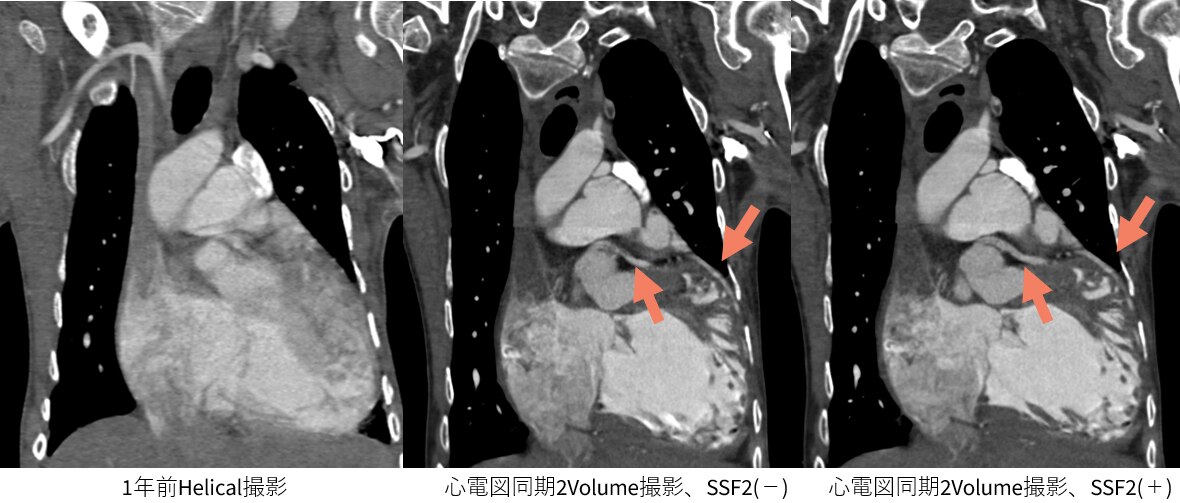

過去の検査時はどうしても至適心位相を探すため、segment再構成等を繰り返し撮影と画像検索を両立するのは困難でした。しかし、最適心位相検索に「Smart Phase」、モーションアーチファクトを抑制する 「SnapShot Freeze2.0(以下SSF2)」を併用することにより、最適心位相の検索をほぼ自動で行えるようになりました。結果、心臓CTの最適心位相検索に時間を割く必要がなくなり、人員配置の最適化を行えるようになると考えています。